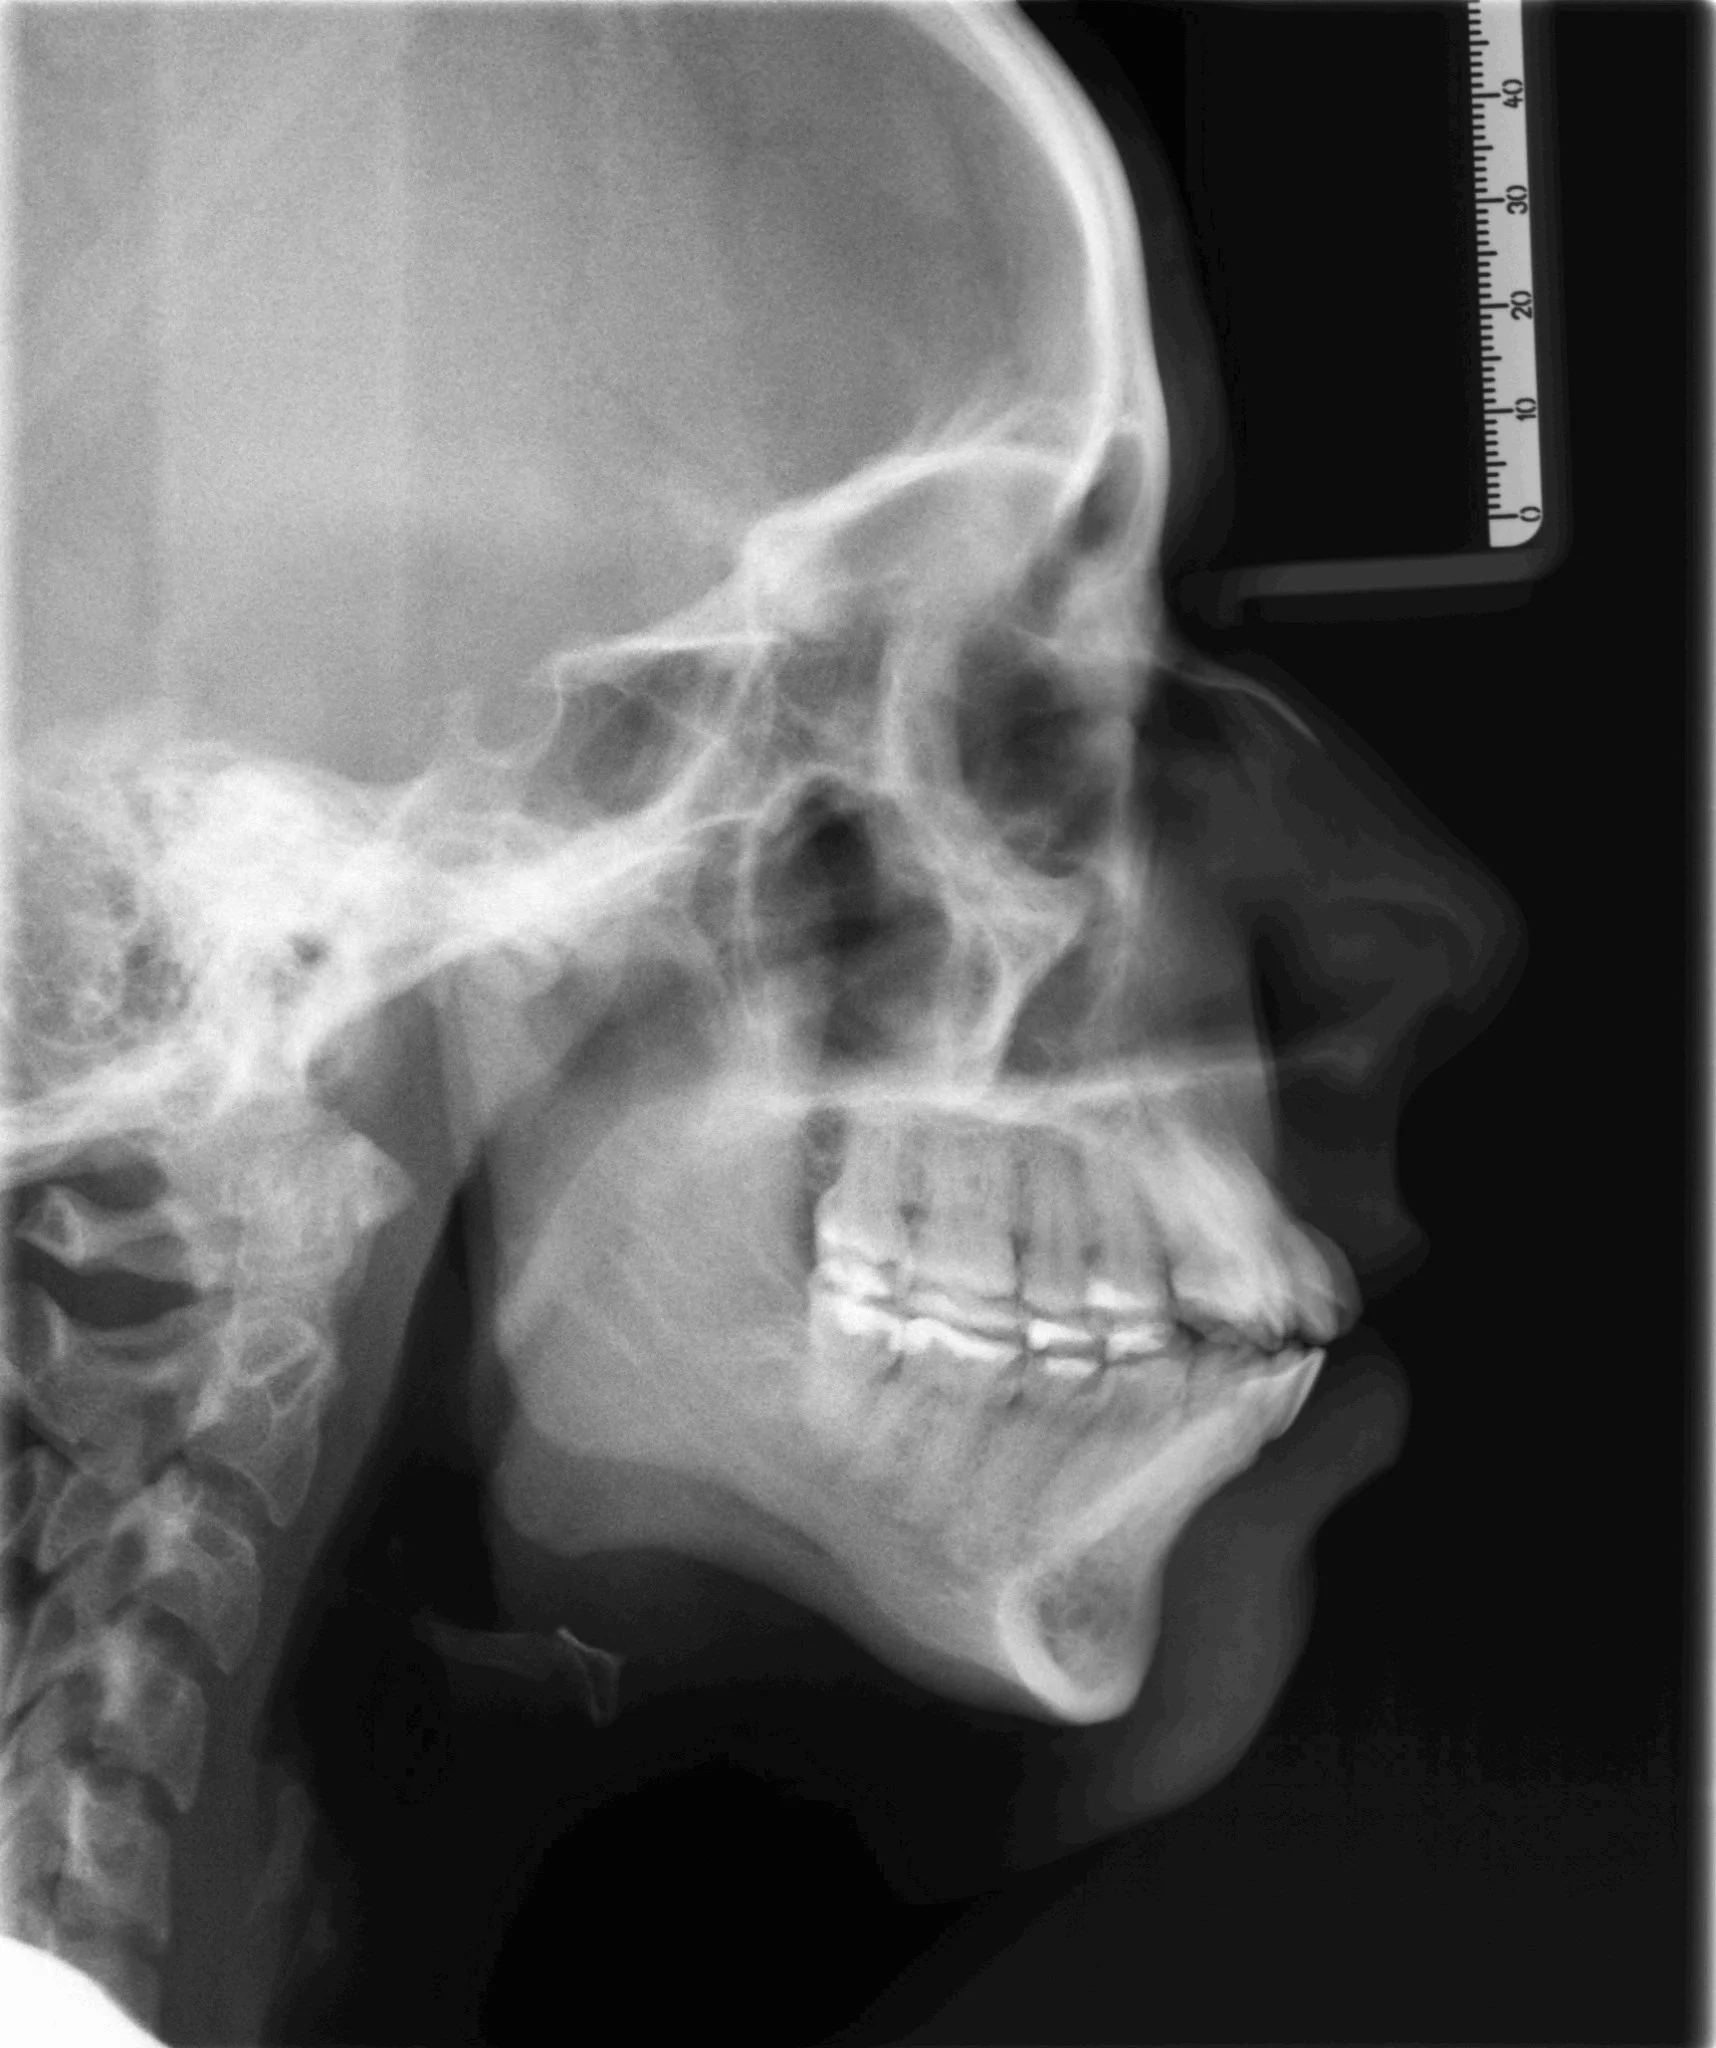

ceph class II.JPG